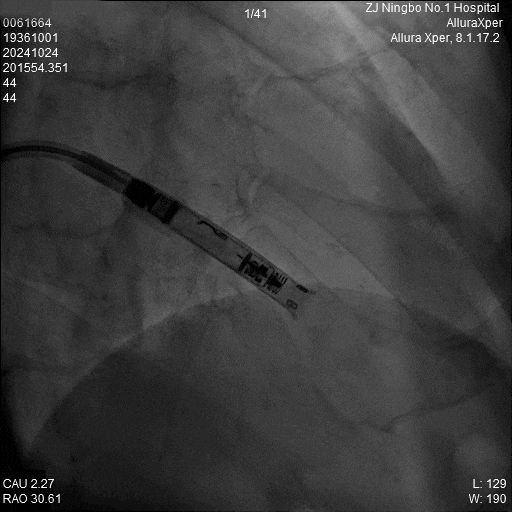

4.旋入起搏器:回撤保护套筒至下腔,释放调弯,调整张力开始旋入旋入0.5圈及1.0圈分别测试参数,等待扭矩传递。